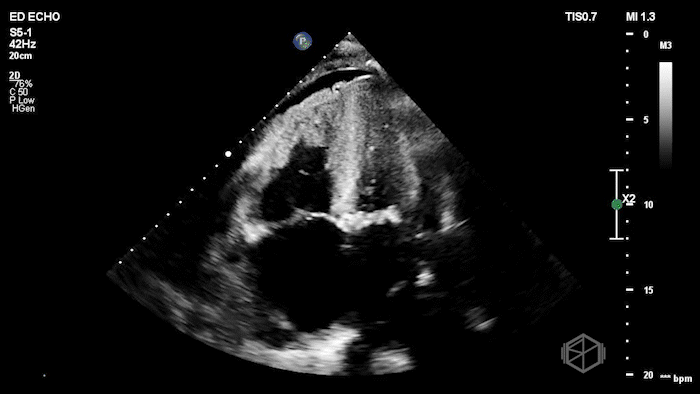

Their Cardiac POCUS showed:

POCUS showed marked left ventricular wall thickening, a dilated right ventricle, biatrial enlargement, a small LV cavity, and a small pericardial effusion. The left ventricular myocardium also had a mildly granular or β€œspeckled” appearance.

Diagnosis: Findings concerning for infiltrative cardiomyopathy (cardiac amyloidosis)